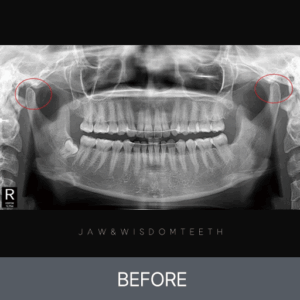

턱관절 CASE